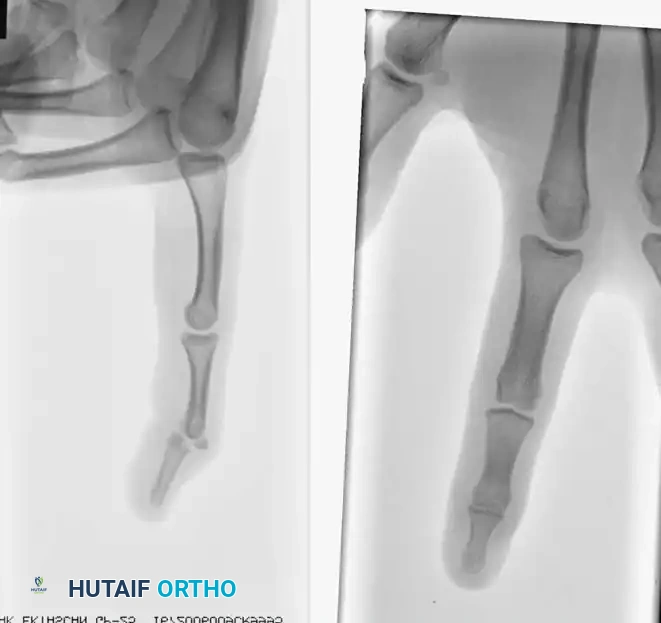

Clinical Case Example

The efficacy of the pull-out wire technique is demonstrated in the management of high-demand athletes.

Fig. 64-65 A, Type 4 mallet fi nger in high school basketball player. B, Results of pull-out wire and pin fi xation of distal interphalangeal joint just before pin removal at 4 weeks. C, Pull-out wire left in until 6 weeks after surgery.

In this scenario, a Type 4 mallet finger in a high school basketball player (A) was treated with pull-out wire and pin fixation. The transarticular pin is typically removed at 4 weeks (B), allowing early protected motion, while the pull-out wire is maintained until 6 weeks postoperatively (C) to ensure solid bony union of the avulsed fragment.